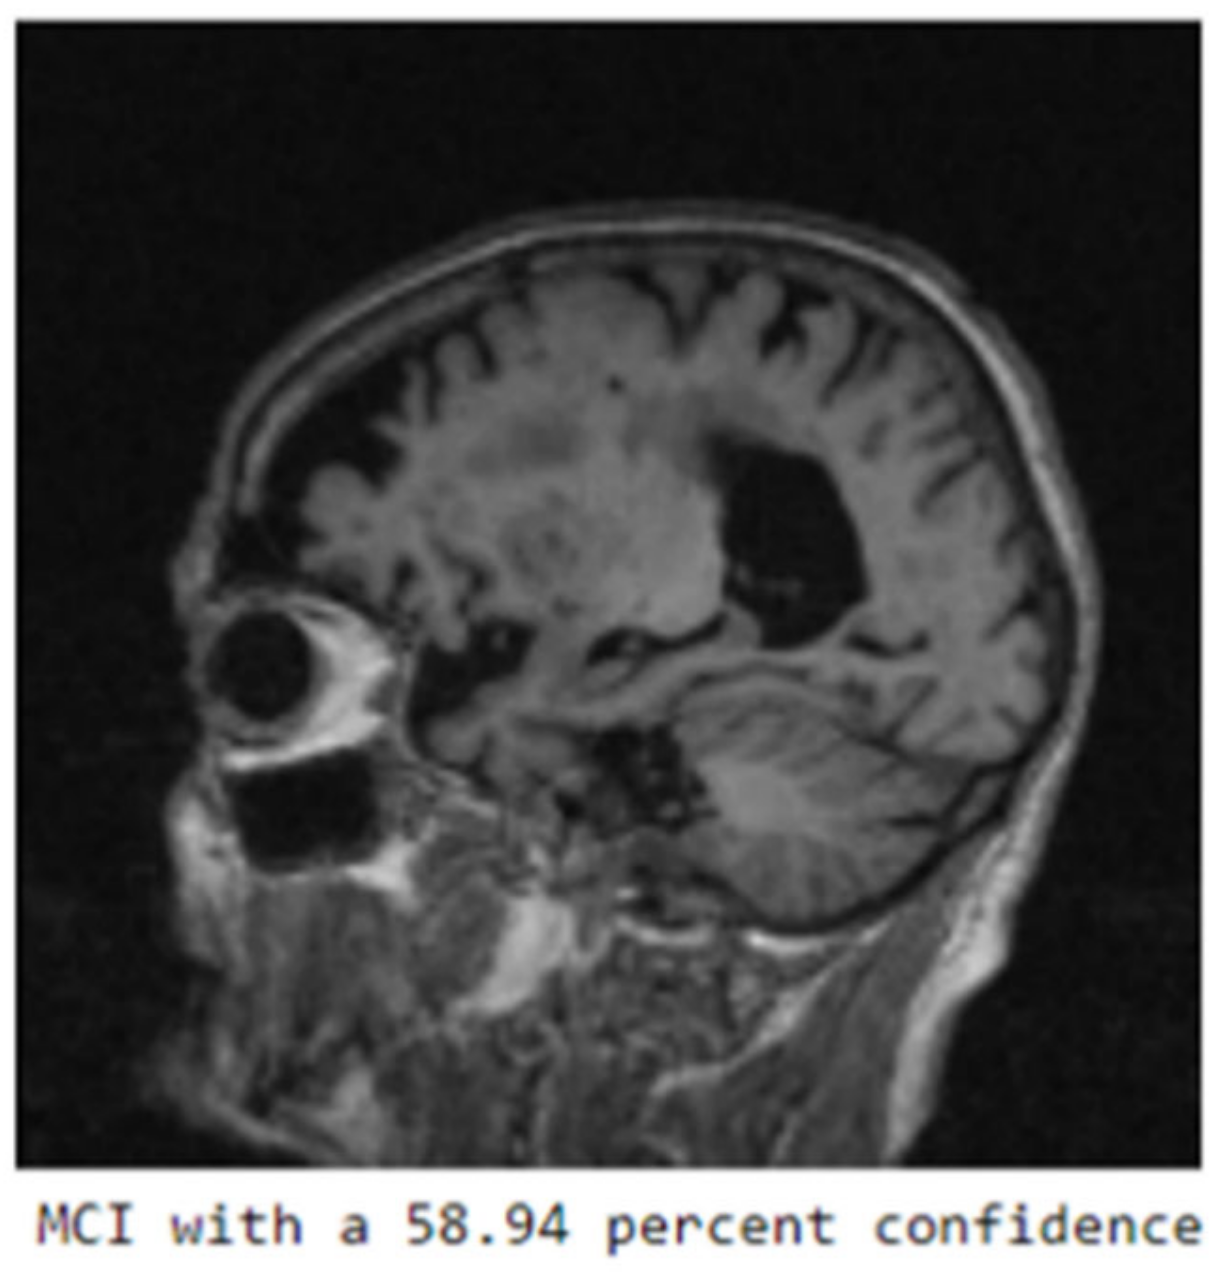

The confusion matrix in Figure 4 displays the network’s predictive performance on the three classes: NC (normal cognition), MCI (mild cognitive impairment), and AD (Alzheimer’s disease). Figure 3 is a visualization of the deep learning model’s performance where the highest training accuracy of 85% is displayed, calculated through Equation (5). The training process was stopped as the model had 0 out of 23,587,712 trainable parameters. Figure 4 visually represents the label predictions using the confusion matrix. One example from the test set produced a positive prediction for mild cognitive impairment (MCI), as shown in Figure 5. This image served as the input for our XAI experiments.

Figure 5. Output prediction from the ResNet-50 model; positive for mild cognitive impairment with 58.94% confidence.